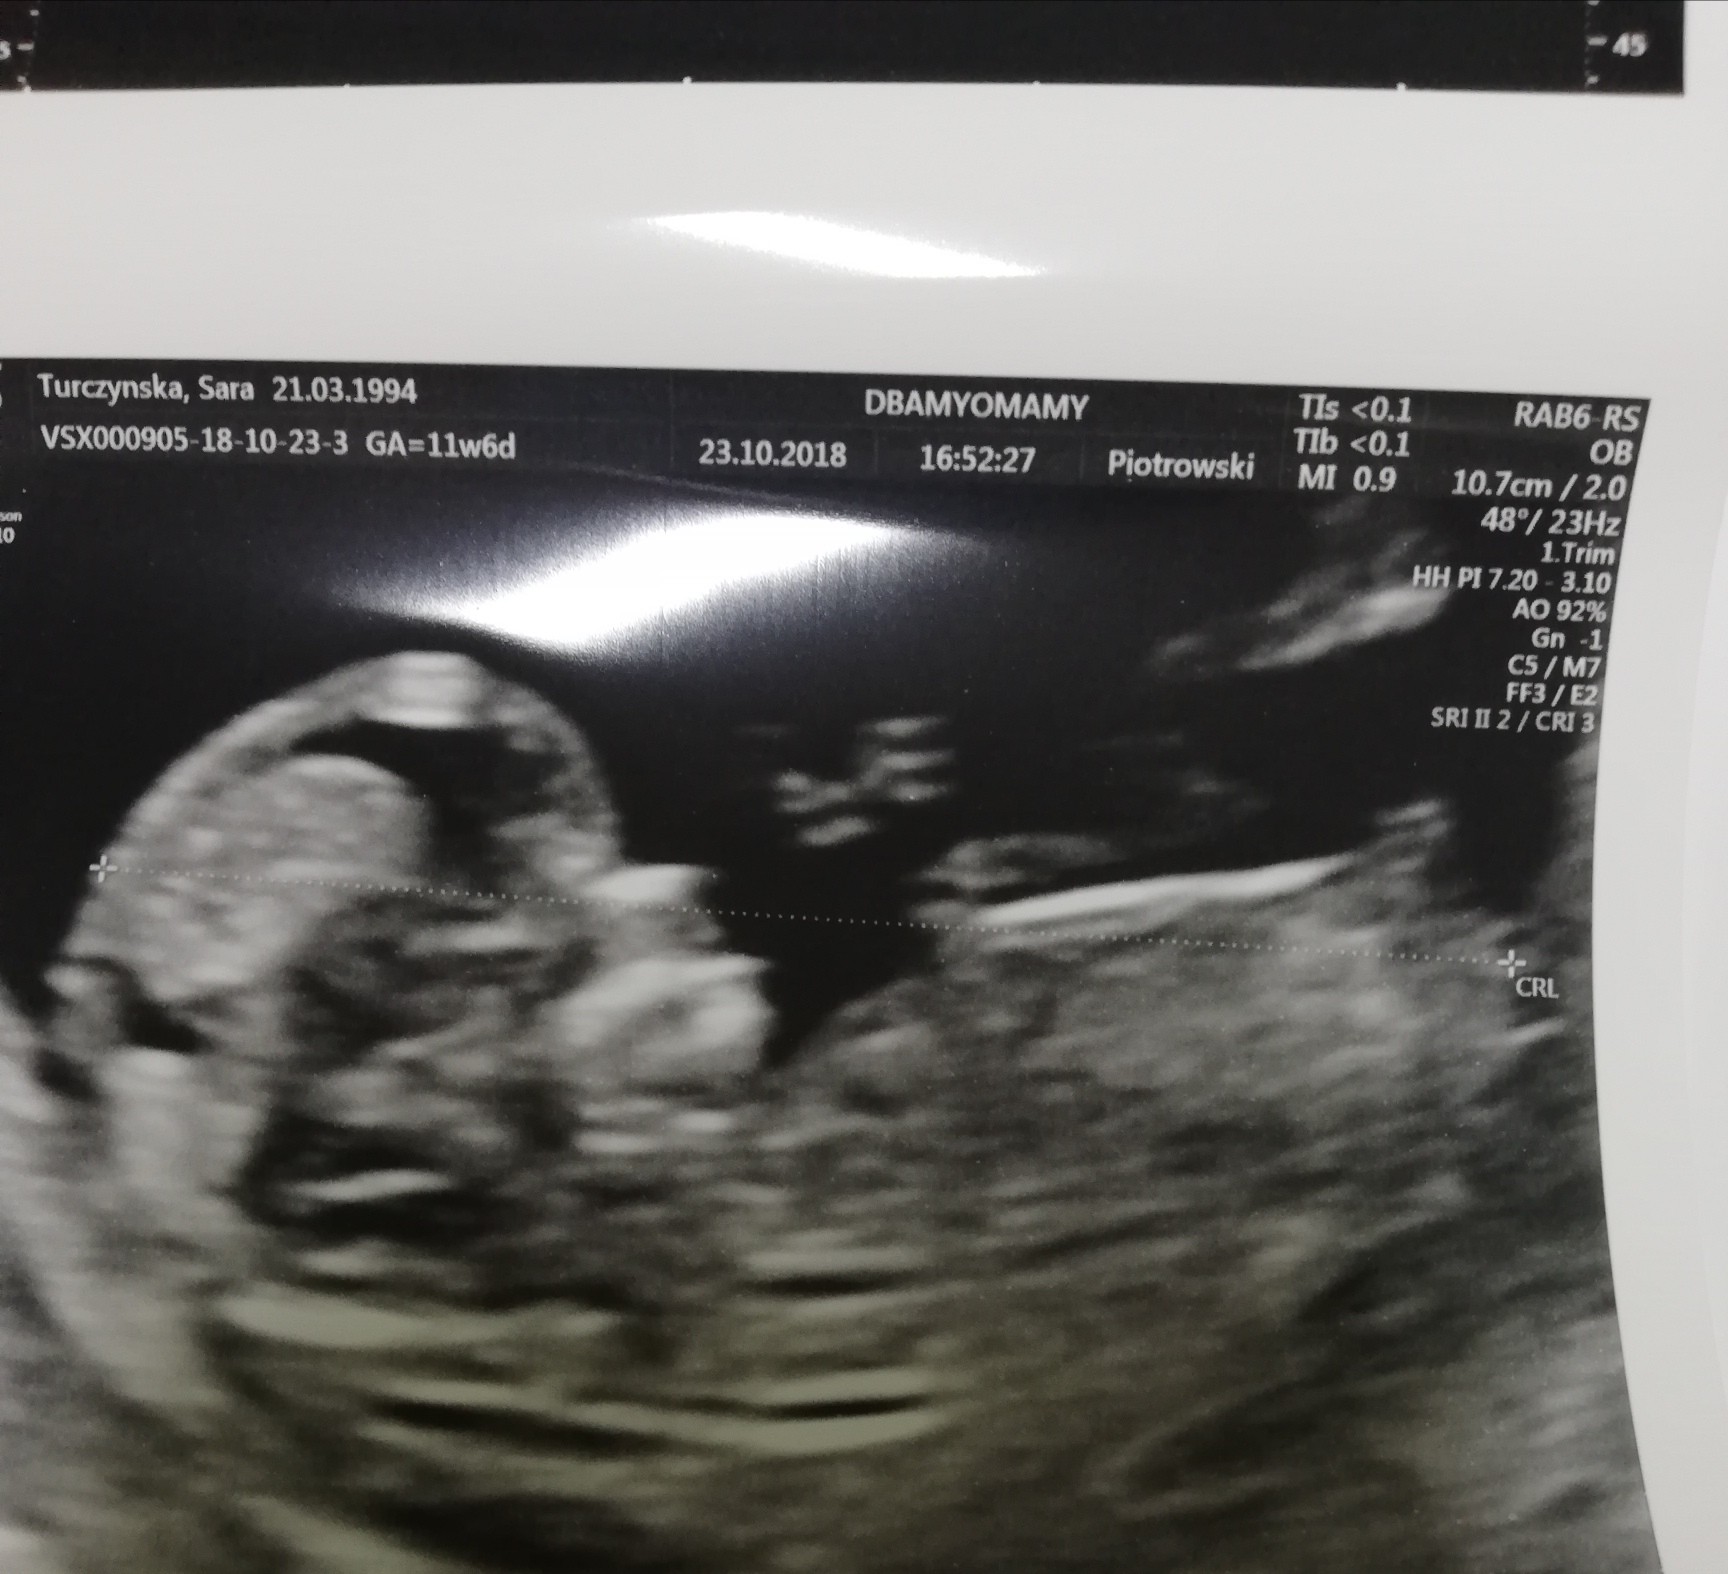

Hej. Dawno tu nie byłam małe zawirowania życiowe We wtorek mieliśmy prenatalne. Wszystko OK, termin na 8 maja (byl 7 , narazie lekarz mówi, że chłopczyk :)

Załączniki

• IMG_20181024_193945.jpg

IMG_20181024_193945.jpg

333,5 KB · Wyświetleń: 177